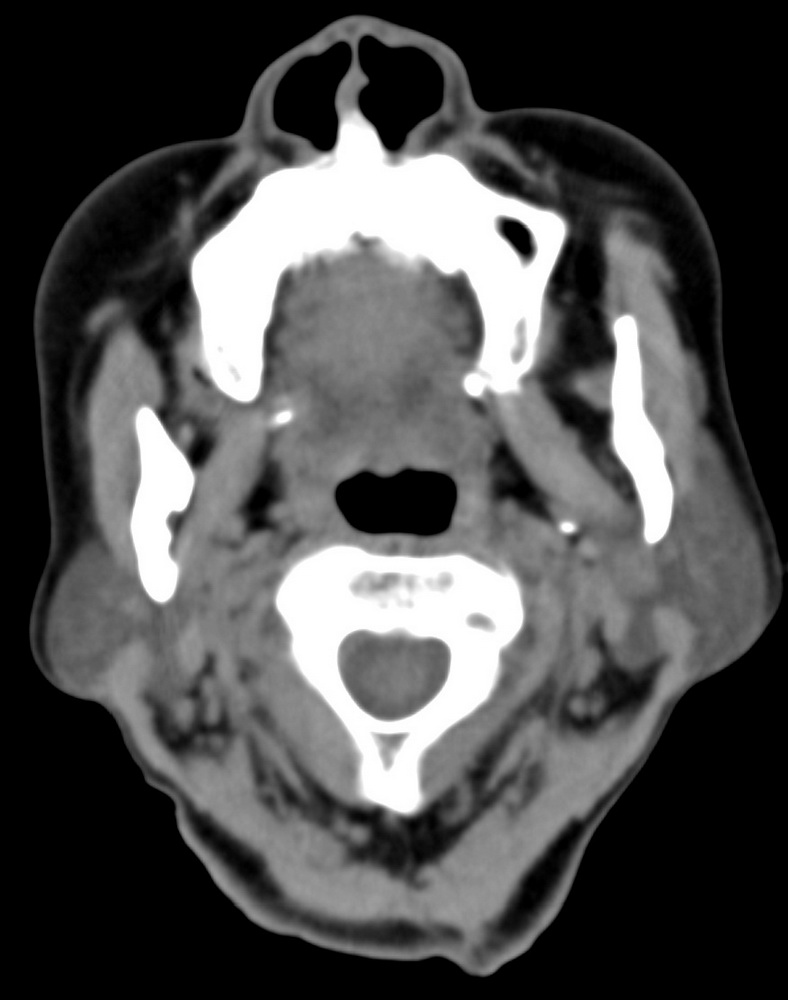

女,68岁。发现上唇无痛性肿块2年多,查体局部皮肤隆起,其余未见异常。

病灶ct值约42hu。

病理结果:唾液腺混合瘤。